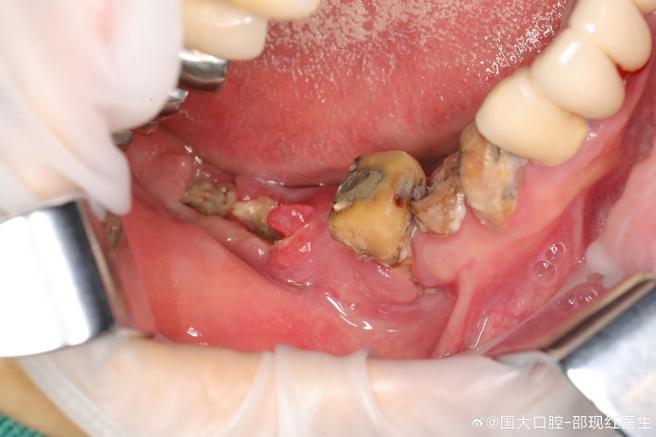

种植体周围炎(种植体失败风险)

- 表现:牙龈红肿、出血、牙周袋形成、种植体松动、X光显示牙槽骨吸收。

- 原因:

- 口腔清洁不当,细菌形成菌斑→牙石→炎症。

- 种植体设计/位置不佳,易堆积食物残渣。

- 糖尿病、吸烟等全身因素影响愈合。